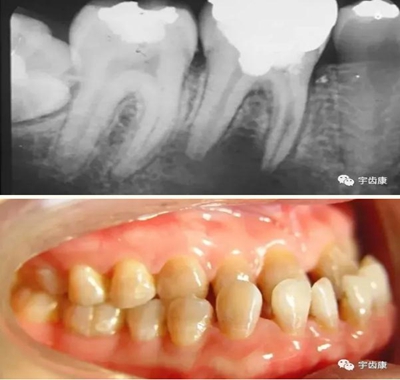

X線閱片知識(shí)